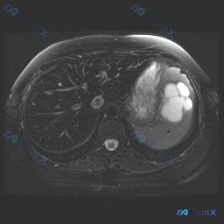

最近看到一张腹部MRI的T2加权轴位片,最初的焦点是“脾脏病变”,但仔细梳理下来,觉得这个病例的阅片思路特别有借鉴意义,整理出来和大家分享。 先看病例的影像客观发现 - 肝脏:右叶可见一处类圆形高信号影,边界清晰锐利,信号均匀; - 脾脏:外后缘可见一处类圆形高信号影,边界清晰,信号均匀; - 左肾...

看到一份很有意思的影像读片案例,用户的问题聚焦在“脾脏病变”,但影像本身却给了我们一个完全不同的方向,整理一下思路和大家分享。 --- 先看影像基本情况 - 序列:腹部MRI T2加权轴位像 - 用户焦点:脾脏病变 关键影像发现(按实际读片顺序) 1. 肝脏、胆囊、胰腺:未见明显异常信号或肿块,胆管...